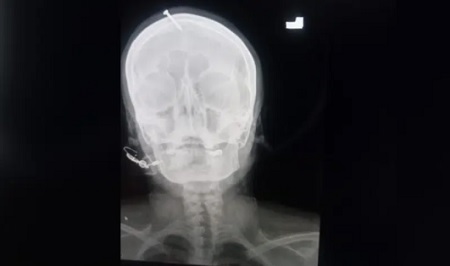

وأظهرت صورة بالأشعة السينية أن المسمار اخترق الجمجمة لمسافة 5 سنتيمترات لكنه لم يصل إلى الدماغ.